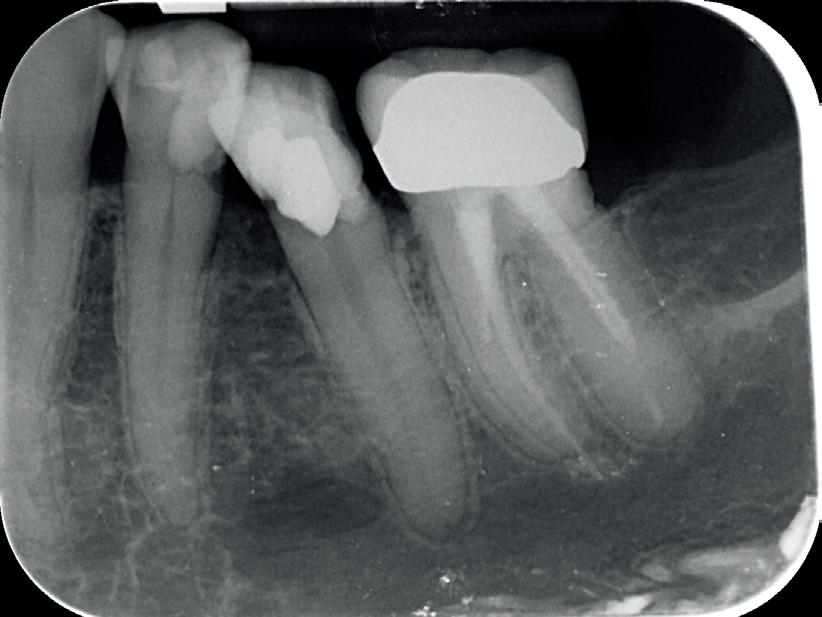

Je kan nu denken, heb ik nu net een gans artikel gelezen van een endodontoloog over hoe ik vooral geen wortelkanaalbehandelingen moet doen? Iemand die zo tegen zijn winkel spreekt kan waarschijnlijk gewoon geen goede wortelkanaalbehandelingen uitvoeren… Deze opmerking heb ik al een aantal keren gehoord wanneer ik een presentatie geef. Meestal begin ik dan ook met het tonen van een zeer uitdagende casus. In dit geval zal ik hetzelfde doen. Foto 1 is een recente wortelkanaalbehandeling die ik uitgevoerd heb. Zowat de natte droom van elke endodontoloog. Nu dat van de baan is, nog enkele voorbeelden uit de praktijk waarbij ik de patiënt centraal heb gezet en soms tegen de vraag van de verwijzende tandarts ben ingegaan.

De verwijzende tandarts wil tanden 24 en 25 overkronen en vraagt evaluatie en eventuele wortel-

kanaalbehandelingen en stiftopbouwen (foto 2). U ziet, mijn verwijzers zijn getraind en vragen eerst een evaluatie of het wel nodig is. Dit heeft me bloed, zweet en tranen gekost, alsook enkele verwijzers. Uiteindelijk bleek tand 24 vitaal te zijn en was er voldoende restweefsel om adhesief te werken. De wortelkanaalbehandeling op de 25 is misschien technisch niet ideaal, maar er zijn geen klachten of radiologische tekenen van infectie. In overleg met de patiënt is dus besloten om tand 24 te voorzien van een stompopbouw en tand 25 van een glasvezelstift en stompopbouw zonder te herbehandelen (foto 3). De tandarts kan onmiddellijk verder met de kronen.